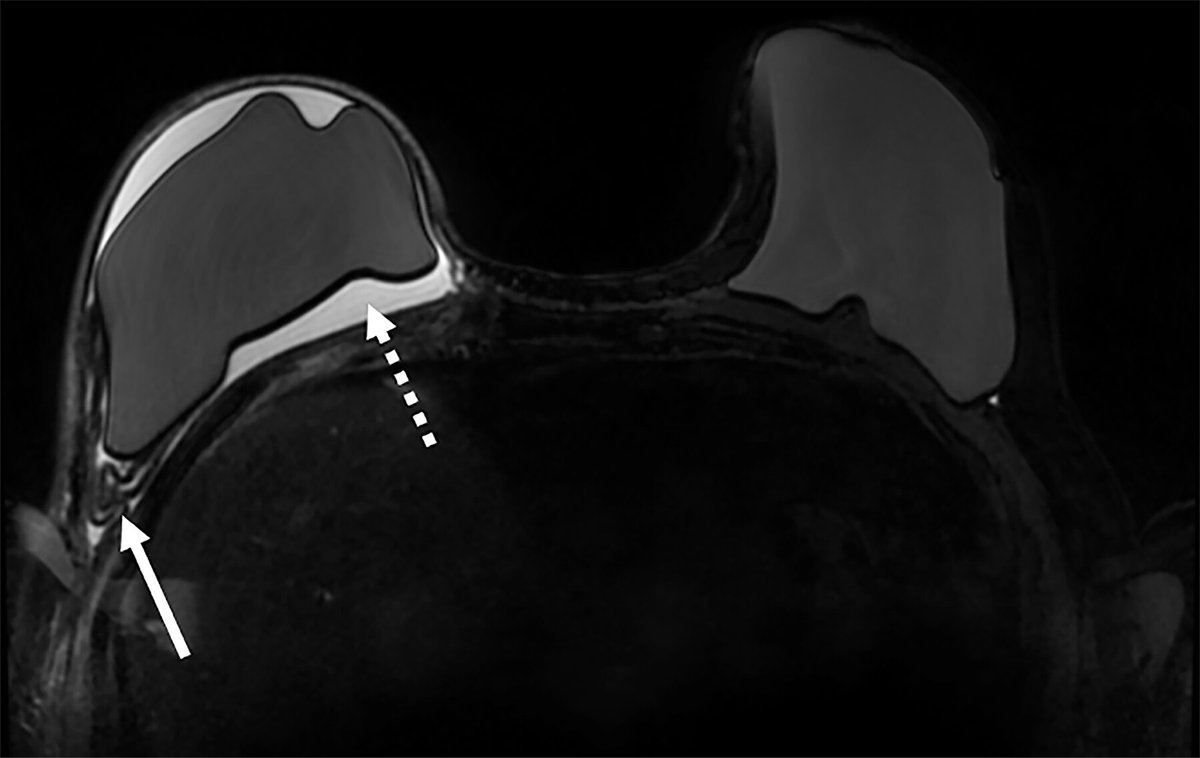

Check out this overview of multimodality imaging of the postmastectomy reconstructed breast, which includes an update on screening guidelines and recommendations for this patient population. Faezeh Sodagari, MD Reni Butler bit.ly/3wsGbuC

Check out this overview of multimodality imaging of the postmastectomy reconstructed breast, which includes an update on screening guidelines and recommendations for this patient population. <a href="/fsodagari/">Faezeh Sodagari, MD</a> <a href="/ButlerReni/">Reni Butler</a> bit.ly/3wsGbuC